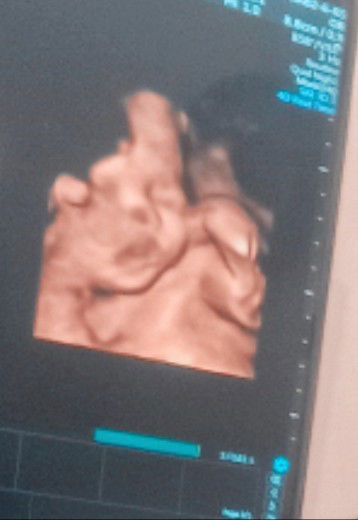

Spill foto USG

Spill foto USG bbj dan hplnya Bun Saya 26 sept baby boy